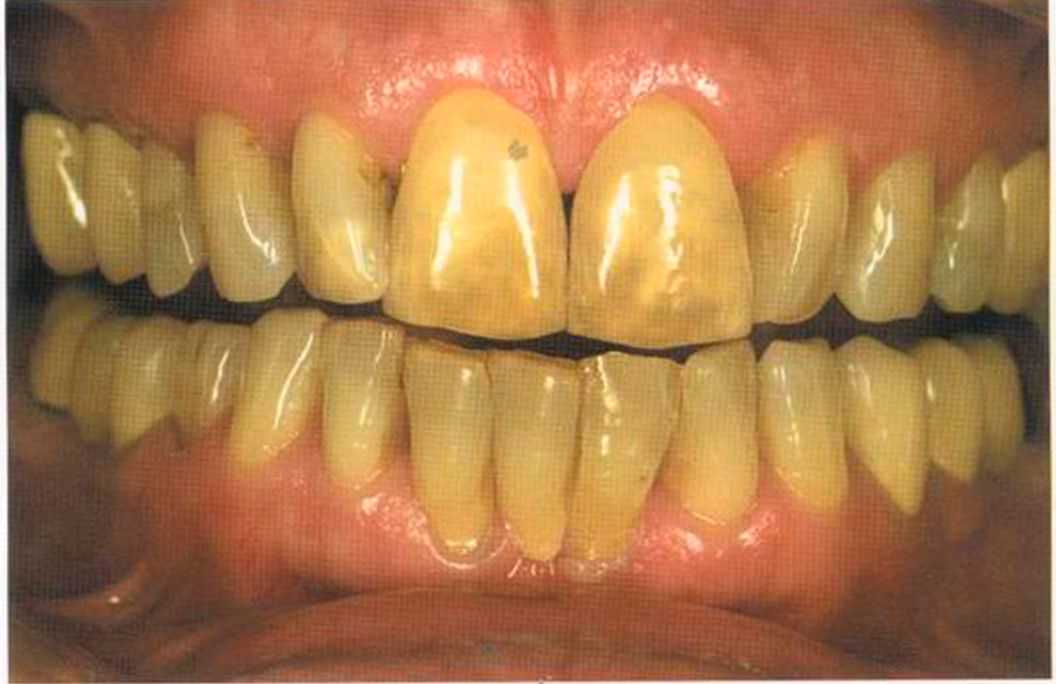

Окончательный результат и естественный цвет губ. Женщина была очень счастлива и довольна своим новым внешним видом. Наконец мечта осуществилась — нет больше этих щелей на видимом участке. Всей нашей команде было очень приятно видеть радость в ее глазах.

Результат с использованием In-Ceram развеял все сомнения, и решение об изготовлении коронки на другой боковой резец не заставило себя долго ждать.

Го то вый результат. Зуб 21 со штифтом из Zirconia. От 12 до 21 изготовлены три отдел1>ные коронки 1п-Сегат. Все зафиксировано в полости рта на цемент Panavia ТС.